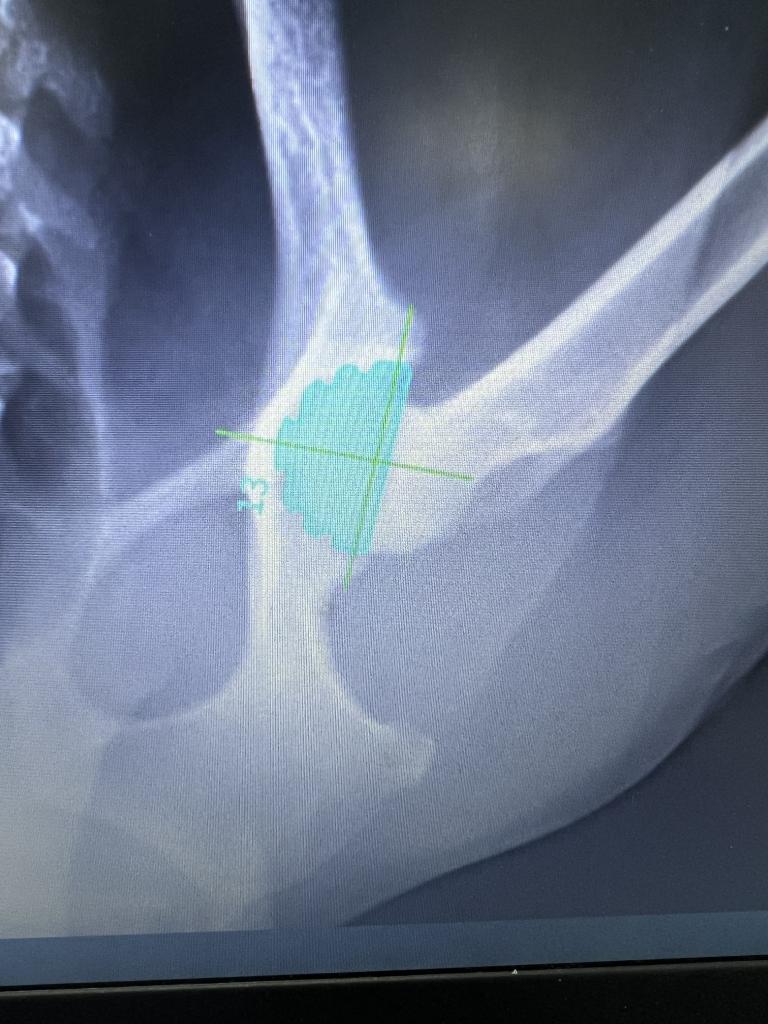

パソコン上で骨の大きさとインプラントのサイズをシュミレーションして術前の準備をします(これは寛骨臼カップ)